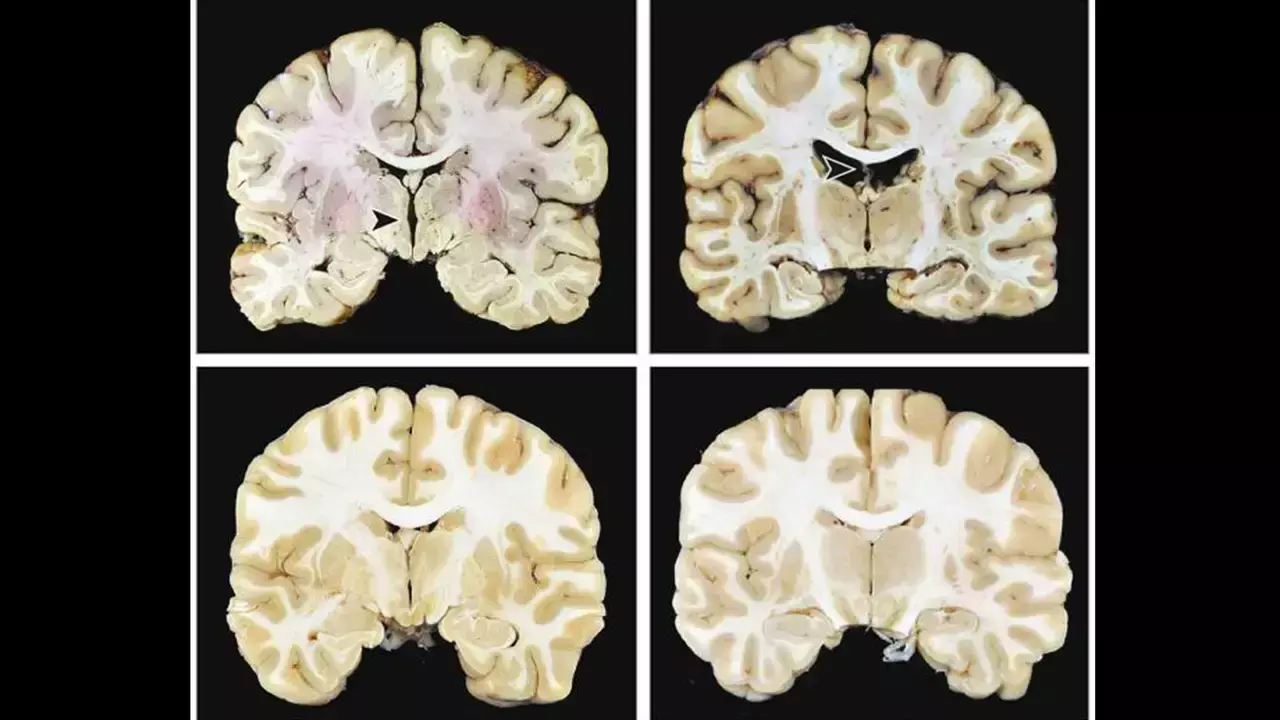

Researchers have found in a large autopsy study of brain donors that without other progressive neurodegenerative diseases, stage III and IV chronic traumatic encephalopathy were associated with significantly higher odds of dementia. In contrast, early-stage (I–II) chronic traumatic encephalopathy showed no association with cognitive symptoms or dementia, indicating that dementia risk rises with advanced chronic traumatic encephalopathy pathology.This studyexamined the independent contribution of chronic traumatic encephalopathy (CTE) neuropathology to symptoms. The sample included 614 brain donors with (n = 366) and without (n = 248) autopsy-confirmed chronic traumatic encephalopathy. Brain donors with other major neurodegenerative disease diagnoses were excluded. Informants completed cognitive and neuropsychiatric measures. Dementia was determined during diagnostic consensus conferences. chronic traumatic encephalopathy stage IV (of IV) was associated with 4.48 (95% confidence interval [CI] = 1.97–10.90) increased odds of having dementia. chronic traumatic encephalopathy stage III had an odds ratio of 2.12 (95% CI = 1.91–3.77). A higher chronic traumatic encephalopathy stage was associated with greater informant-reported cognitive symptoms (p < 0.01). There were no associations with mood/behavioural scales. Chronic traumatic encephalopathy stage III/IV neuropathology was associated with dementia and cognitive symptoms: those with stage IV were 4.5 times more likely to have dementia than those without chronic traumatic encephalopathy. It is uncertain if low-stage chronic traumatic encephalopathy clinically manifests, and mood/behavioural symptoms likely have multifactorial causes and/or a fluctuating course.Stage III and IV chronic traumatic encephalopathy (CTE) are independently associated with increased odds of having dementia. Thus, to conclude a higher chronic traumatic encephalopathy stage was associated with greater informant-reported cognitive symptoms.Stage I and II chronic traumatic encephalopathy were not associated with cognitive symptoms or dementia. Chronic traumatic encephalopathy of any severity was not associated with informant-reported mood or behavioural symptoms.Reference:Layden RM, Groh JR, Miner AE, et al. CTE neuropathology alone is associated with dementia and cognitive symptoms. Alzheimer’s Dement. 2026; 22:e71032. https://doi.org/10.1002/alz.71032Keywords:Layden RM, Groh JR, Miner AE, CTE, neuropathology, alone, associated, dementia, cognitive symptoms